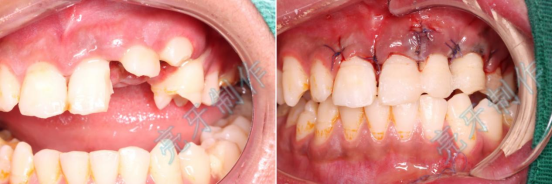

病例二:外伤导致上牙槽骨骨折,而且上下两颗门牙脱位;通过治疗,上下两颗门牙均恢复原来位置,而且和之前一样结实。